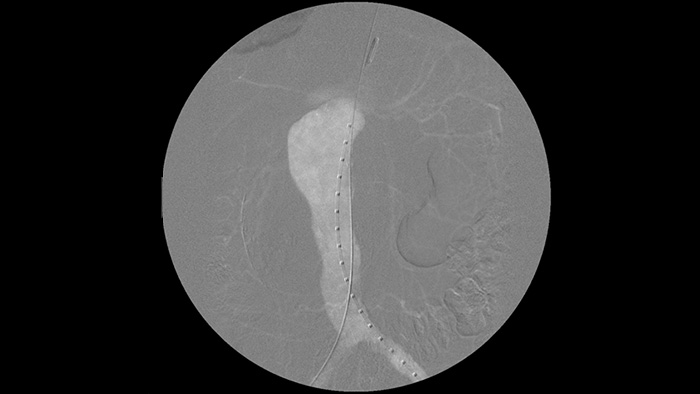

Die digitale Subtraktionsangiographie (DSA) ist bei interventionellen Gefässeingriffen besonders hilfreich. Bei diesem Verfahren werden Strukturen ausgeblendet, die Blutgefässe verdecken, um die Gefässe möglichst klar darzustellen. Zuvor unter Kontrastmitteleinsatz erfasste, subtrahierten Bilder werden mit dem Live-Durchleuchtungsbild überlagert (Roadmapping), sodass Sie Instrumente ohne erneute Kontrastmittelinjektion ungehindert verfolgen können.

„Mit dem Zenition hat sich unsere DSA-Bildqualität stark verbessert. Es gibt keine unscharfen Bilder mehr, nur noch sehr Klare.“

„Im Vergleich zu unserem vorherigen System sind Führungsdrähte dadurch einfacher zu erkennen: Es sind nun auch Spitze und Winkel des Drahts sichtbar, selbst bei Drähten mit einer Stärke von nur 0,36 mm. Das liegt daran, dass Zenition Metall- und Bewegungsartefakte ausgleicht.“